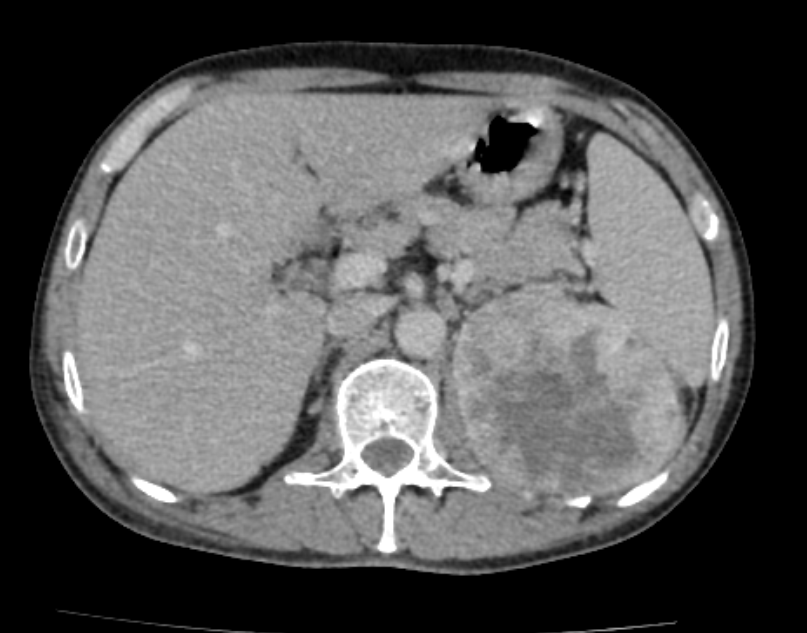

- Visualized sections of upper abdomen show a large enhancing mass with central necrotic areas in left hypochondrium region ,measures approximately 8 x 8 cm . Mass is situated posterior to stomach and posteromedial to lower pole of spleen. Regional lymphadenopathy is noted -Likely malignant left renal mass.

Malignant left renal mass with multiple lung and bony metastasis as described above.